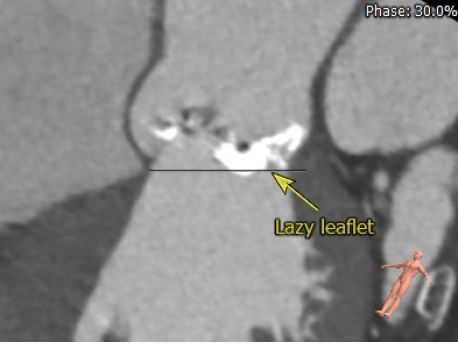

患者17年前因肺结核行左肺叶切除,术前CT结果显示,心脏转位完全偏至左侧胸腔,主动脉弓被挤压成角非常锐利。患者为二叶式主动脉瓣 Type 1型,R-L融合大块钙化脊,且钙化赘生物垂坠至瓣环平面,导致“lazy leaflet”瓣叶结构,主动脉根部极重度钙化,风险度极高,球囊扩张时合并极高的瓣环破裂风险,也可能无法推动钙化使瓣膜形态变形导致严重瓣周漏等并发症。瓣环面积为588.8mm2,平均内径为27.4mm。考虑到患者已行开胸手术,身体虚弱,外科手术风险较高,且介入治疗可更快恢复,减少住院时间,经心脏团队讨论,并与家属协商后,计划行经导管主动脉瓣置换术。

图2. 主动脉根部极重度钙化与lazy leaflet结构